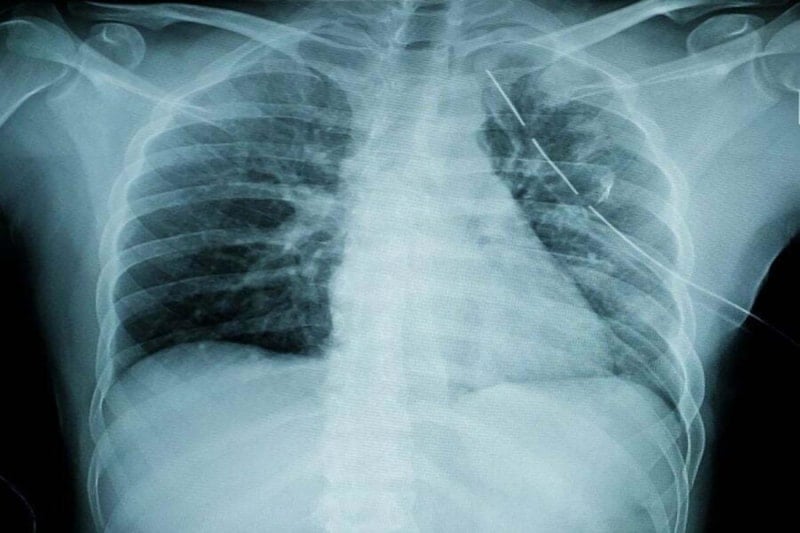

İman tahtası, göğüs kemiği veya iman tahtası kemiği olarak da bilinen sternumun halk arasındaki adıdır.

Sağ ve sol kaburga kemiklerini bir arada tutan göğüs kafesi kemiği, iman tahtasıdır.

İman tahtası, vücudun birçok önemli yapısını koruyan ve destekleyen bir kemiktir.

Hayati organların korunması: Kalp ve akciğerler gibi hayati organları korur.